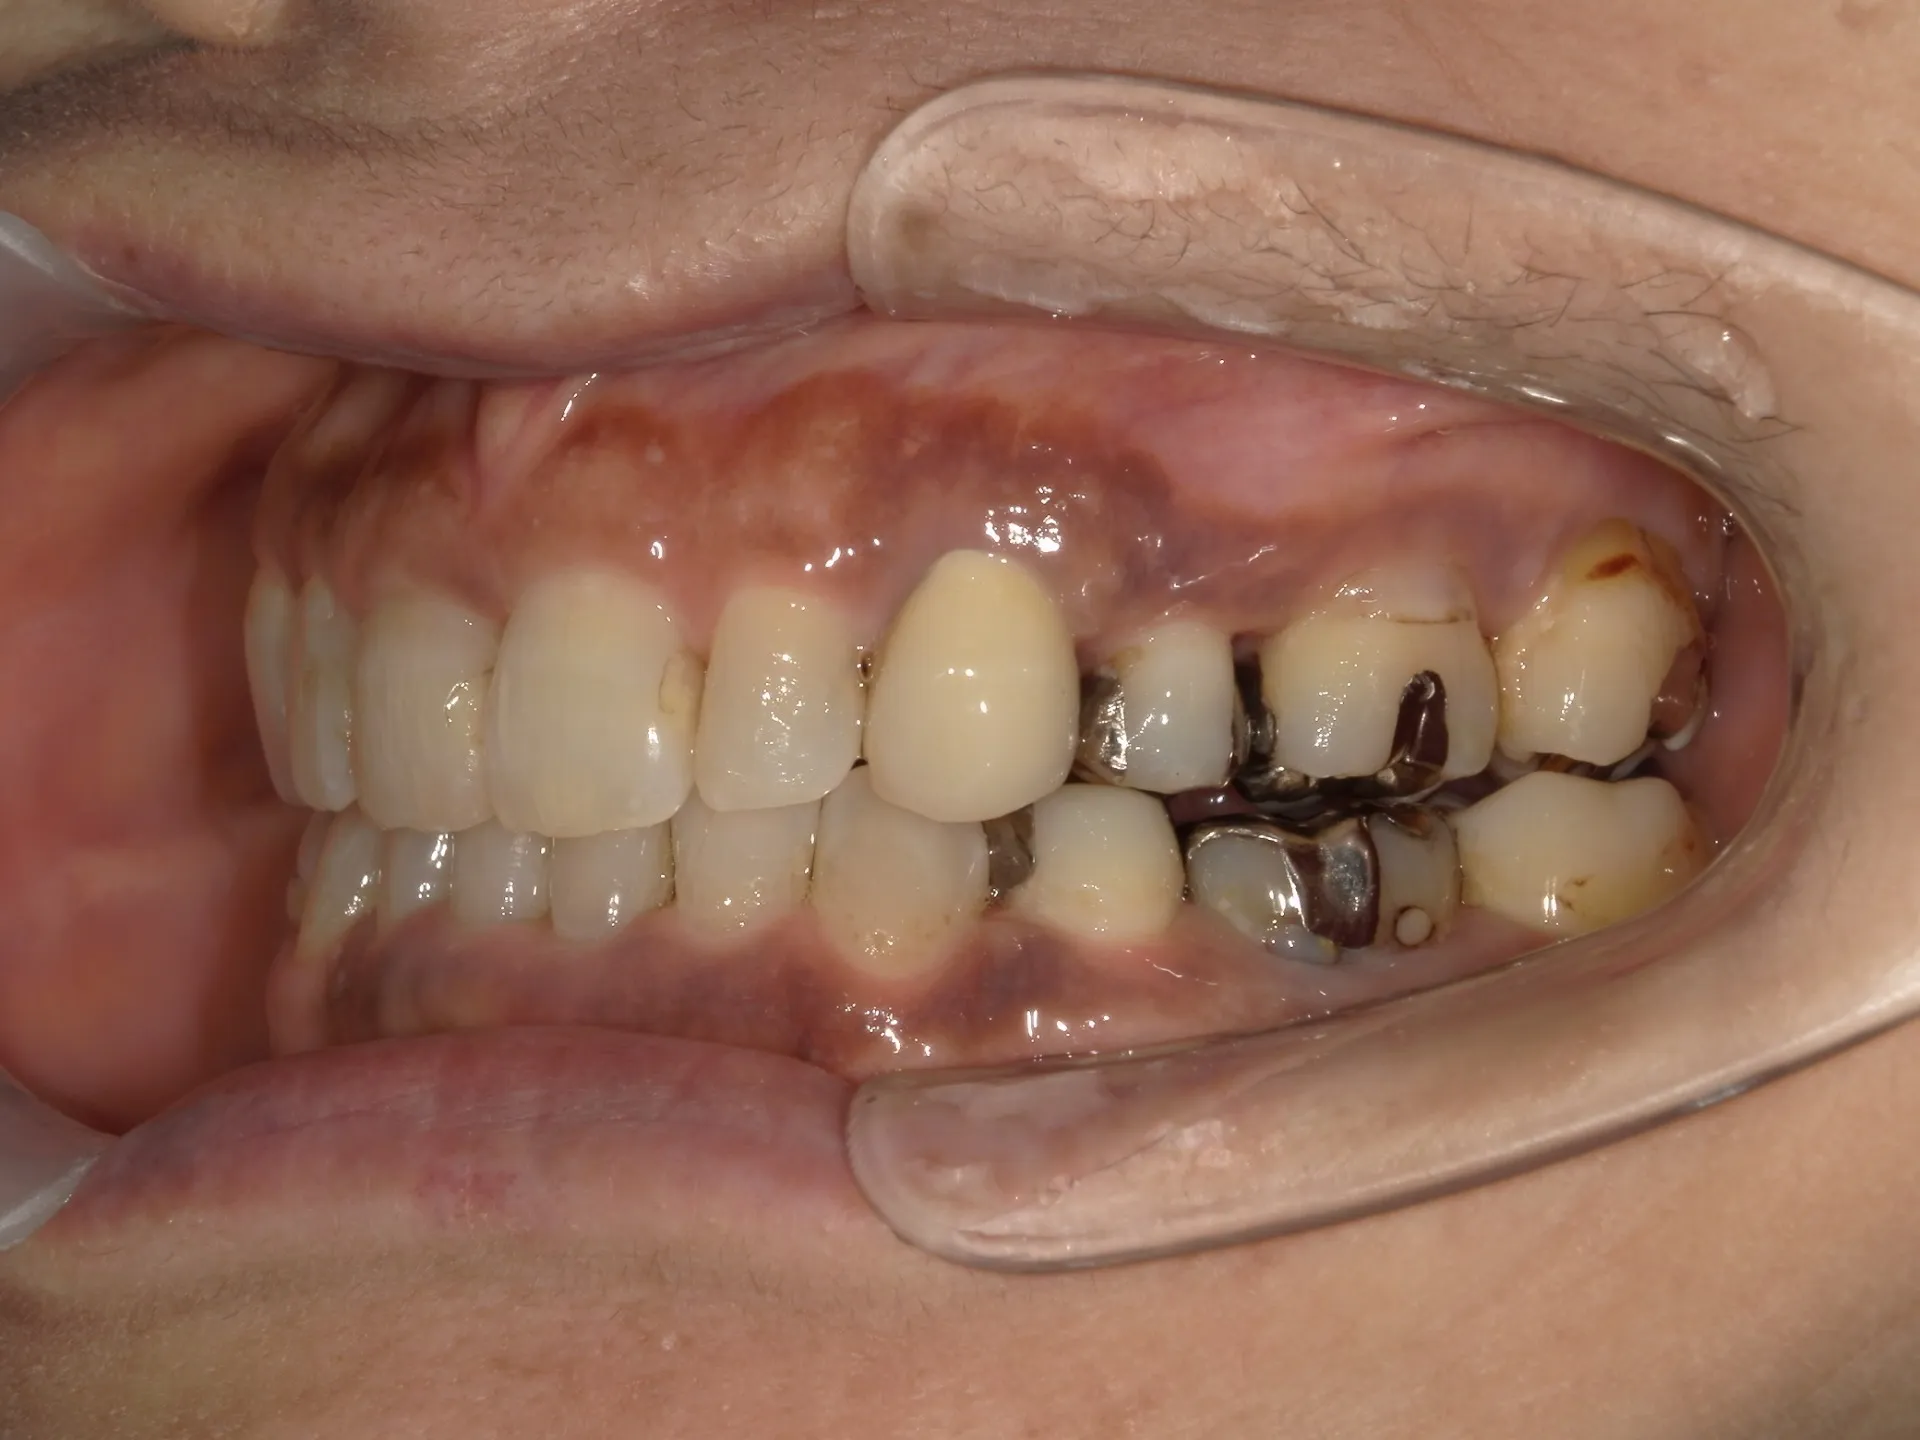

今回は65歳以上でも矯正治療を開始した症例についてご紹介いたします。

しかし、年齢がたとえ定年を迎えたあとであっても十分に矯正が行えて、今後の歯磨きが容易になり、虫歯や歯周病のリスクが減らせて歯を残すことが出来たり、歯並びが良くなったことでモチベーションも上がるなどの矯正後のメリットも非常に高いため、健康的な生活を行う上でも矯正治療は行うことをお勧めします。